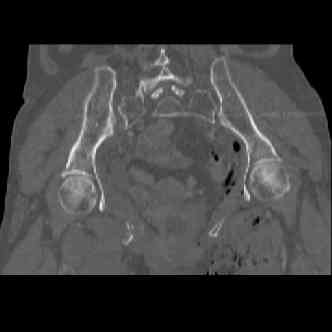

attached are several CT cuts. please let me know if you need more. the CT is pre-pelvic ex-fix placement.